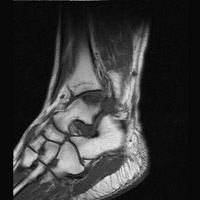

D D | Sagittal MRI. This T1-weighted image shows a region of low signal intensity representing the site of osteochondritis dissecans and edema. |